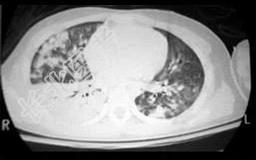

- 单项选择题24岁,男, 车祸后呼吸困难,CT检查如图, 请选出最可能的诊断 ( )

A、肺结核

B、肺转移瘤

C、肺挫伤

D、肺撕裂伤

E、尘肺